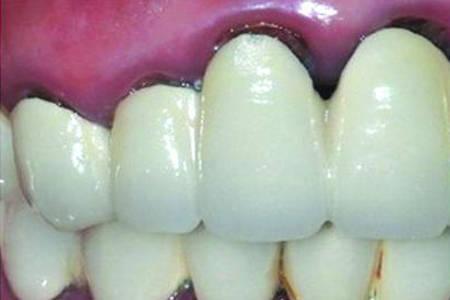

镍铬合金烤瓷牙这牙龈黑线确实有点不好看呢▼

劣质烤瓷冠导致牙龈黑线